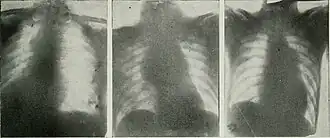

_(14570836478).jpg)

Chest radiograph showing the presence of pulmonary arterial aneurysm. This is often employed in the diagnosis of the disease and allows for detecting the severity.